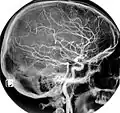

Magnetic Resonance Angiography -

Normal carotidal arteriography